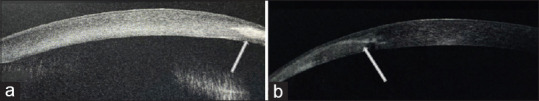

Peripheral ulcerative keratitis (PUK) is characterized by epithelial destructive lesions in the perilimbal cornea causing corneal thinning. It is an inflammatory condition commonly associated with systemic autoimmune disorders and mainly found in middle-aged females. It is a sight threatening entity with potential for severe visual impairment or loss of eye. Recognition of ocular manifestations of PUK is essential especially in the younger age group, as it is difficult to diagnose in a child. We present a unique case of a 13-year-old girl with bilateral PUK and later diagnosed with juvenile idiopathic arthritis. She was started on methotrexate tablets to control the systemic disease and advised continuation of topical cyclosporine eye drops.